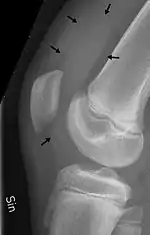

Imaging

An X-ray is useful to verify that there is no break or dislocation when there is a history of trauma. May show signs of osteoarthritis.